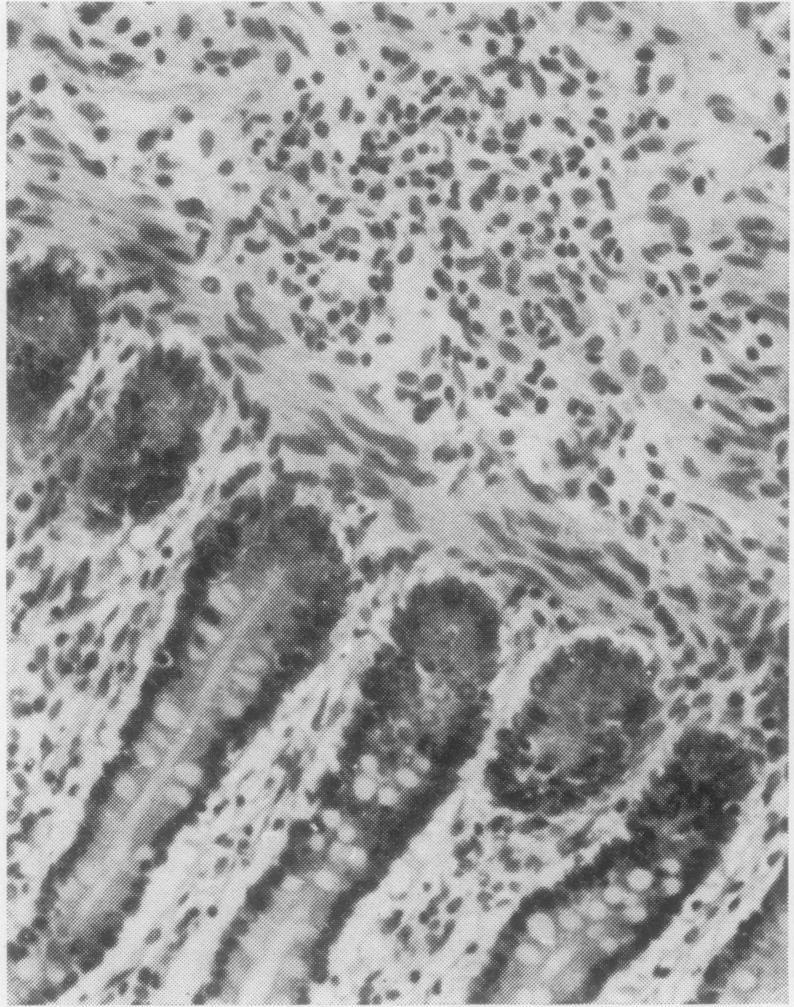

The histopathological appearances of the thymus, lymph nodes, spleen, and gut-associated lymphoid tissue (tonsil, Peyer's patches, and appendix) in cases of the combined immunity-deficiency syndrome are presented. The appearance of tissues remaining after foetal thymic transplants and the effects of such transplants on the morphology of lymph nodes are also discussed. Although thymic appearances are remarkably constant the picture in the lymph nodes and spleen may vary considerably. The tonsils, Peyer's patches, and appendix appear to constitute one lymphoid organ in man, at least with regard to the developmental arrest that may occur in this syndrome.

本文呈现了联合免疫缺陷综合征病例中胸腺、淋巴结、脾脏及肠道相关淋巴组织(扁桃体、派伊尔结和阑尾)的组织病理学表现。还讨论了胎儿胸腺移植后剩余组织的外观以及此类移植对淋巴结形态的影响。尽管胸腺的表现非常一致,但淋巴结和脾脏的情况可能有很大差异。扁桃体、派伊尔结和阑尾在人类中似乎构成一个淋巴器官,至少就该综合征可能出现的发育停滞而言是这样。